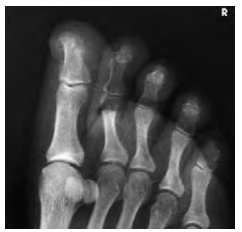

Structures shown (보여지는 해부학 구조들)

AP oblique 투사를 통해 얻는 영상은 다음과 같은 구조를 포함합니다:

- 발가락의 지골(Phalanges)

- 발등뼈의 원위부(Distal portion of metatarsals)

- 약간 내측으로 회전된 발 구조

Evaluation criteria (평가 기준)

- 발가락 전체가 포함되어야 하며, 발등뼈의 원위부도 시각화되어야 합니다.

- 발가락이 서로 분리되어 있어야 합니다.

- 지골의 회전이 없어야 하며, 연부조직의 폭과 중앙 오목한 부분이 대칭적으로 나타나야 합니다.

- IP 및 MTP 관절 공간이 열려 있어야 합니다.

- 연부조직과 뼈의 세부 구조가 뚜렷해야 합니다.